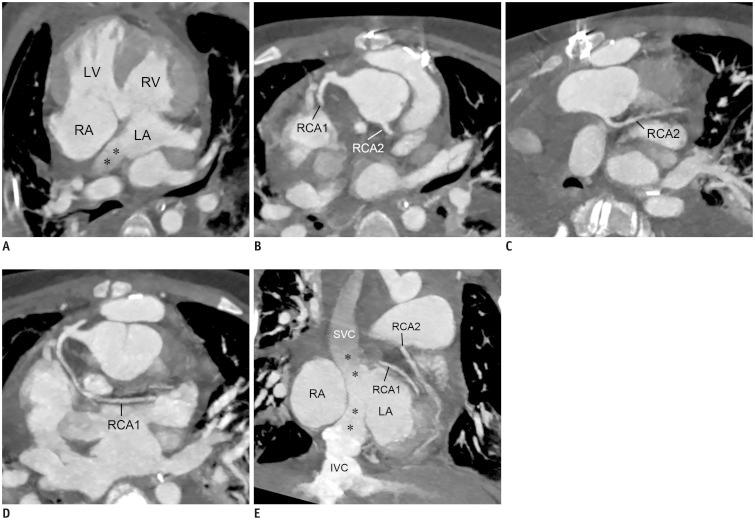

Coronary artery problems in children usually have a significant impact on both short-term and long-term outcomes. Early and accurate diagnosis, therefore, is crucial but technically challenging due to the small size of the coronary artery, high heart rates, and limited cooperation of children. Coronary artery visibility on CT and MRI in children is considerably improved with recent technical advancements. Consequently, CT and MRI are increasingly used for evaluating various congenital and acquired coronary artery abnormalities in children, such as coronary artery anomalies, aberrant coronary artery anatomy specific to congenital heart disease, Kawasaki disease, Williams syndrome, and cardiac allograft vasculopathy.